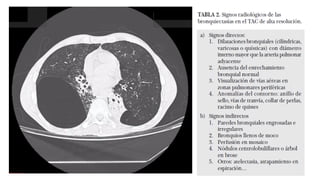

DIAGNOSTICO

• Datos clínicos y la radiografía de tórax,

• Confirmatorio  tac de alta resolución

Dependiendo de la etapa en que se pesquisa se vera una variada

gama de severidad de lesiones.

DIAGNOSTICO • Datos clínicosy la radiografía de tórax, • Confirmatorio  tac de alta resolución Dependiendo de la etapa en que se pesquisa se vera una variada gama de severidad de lesiones.